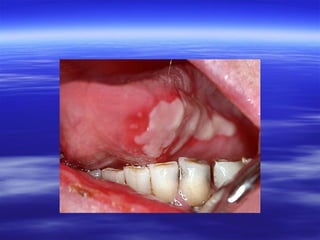

Acute Pseudomembranous

(Candidosis (Thrush

Clinical Features:

 Painless, soft, friable, and creamy plaques on the

mucosa.

 Can be easily wiped off, to expose an

erythematous mucosa or shallow ulceration.

 Their extent varies from isolated small flecks to

widespread confluent plaques.

 Angular stomatitis is frequently associated as it is

with any form of intra-oral candidosis.

 Sometimes a prodrome of bad taste or loss of taste

sensation precedes the appearance of the lesions.